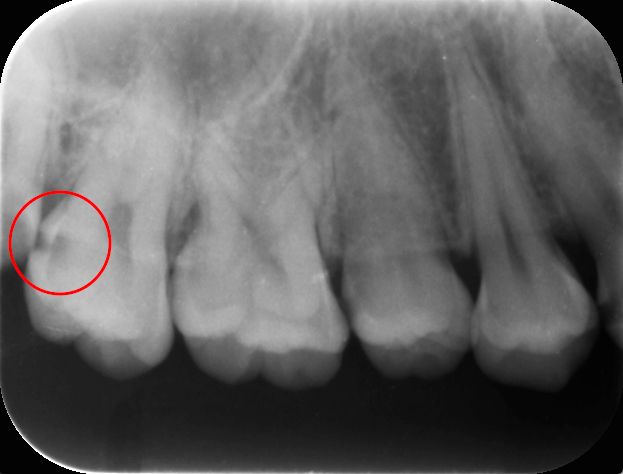

つぎはべつの患者さんのレントゲン写真です。

赤い丸が虫歯です赤い丸の右側の虫歯はとても大きく進行している虫歯です。

この患者さんは歯の神経まで虫歯が進行してしまいとても痛くなり歯医者に来ました。

残念ながら神経をとる治療となりました。

歯の神経をとることはその歯の寿命をとても短くしてしまいます。